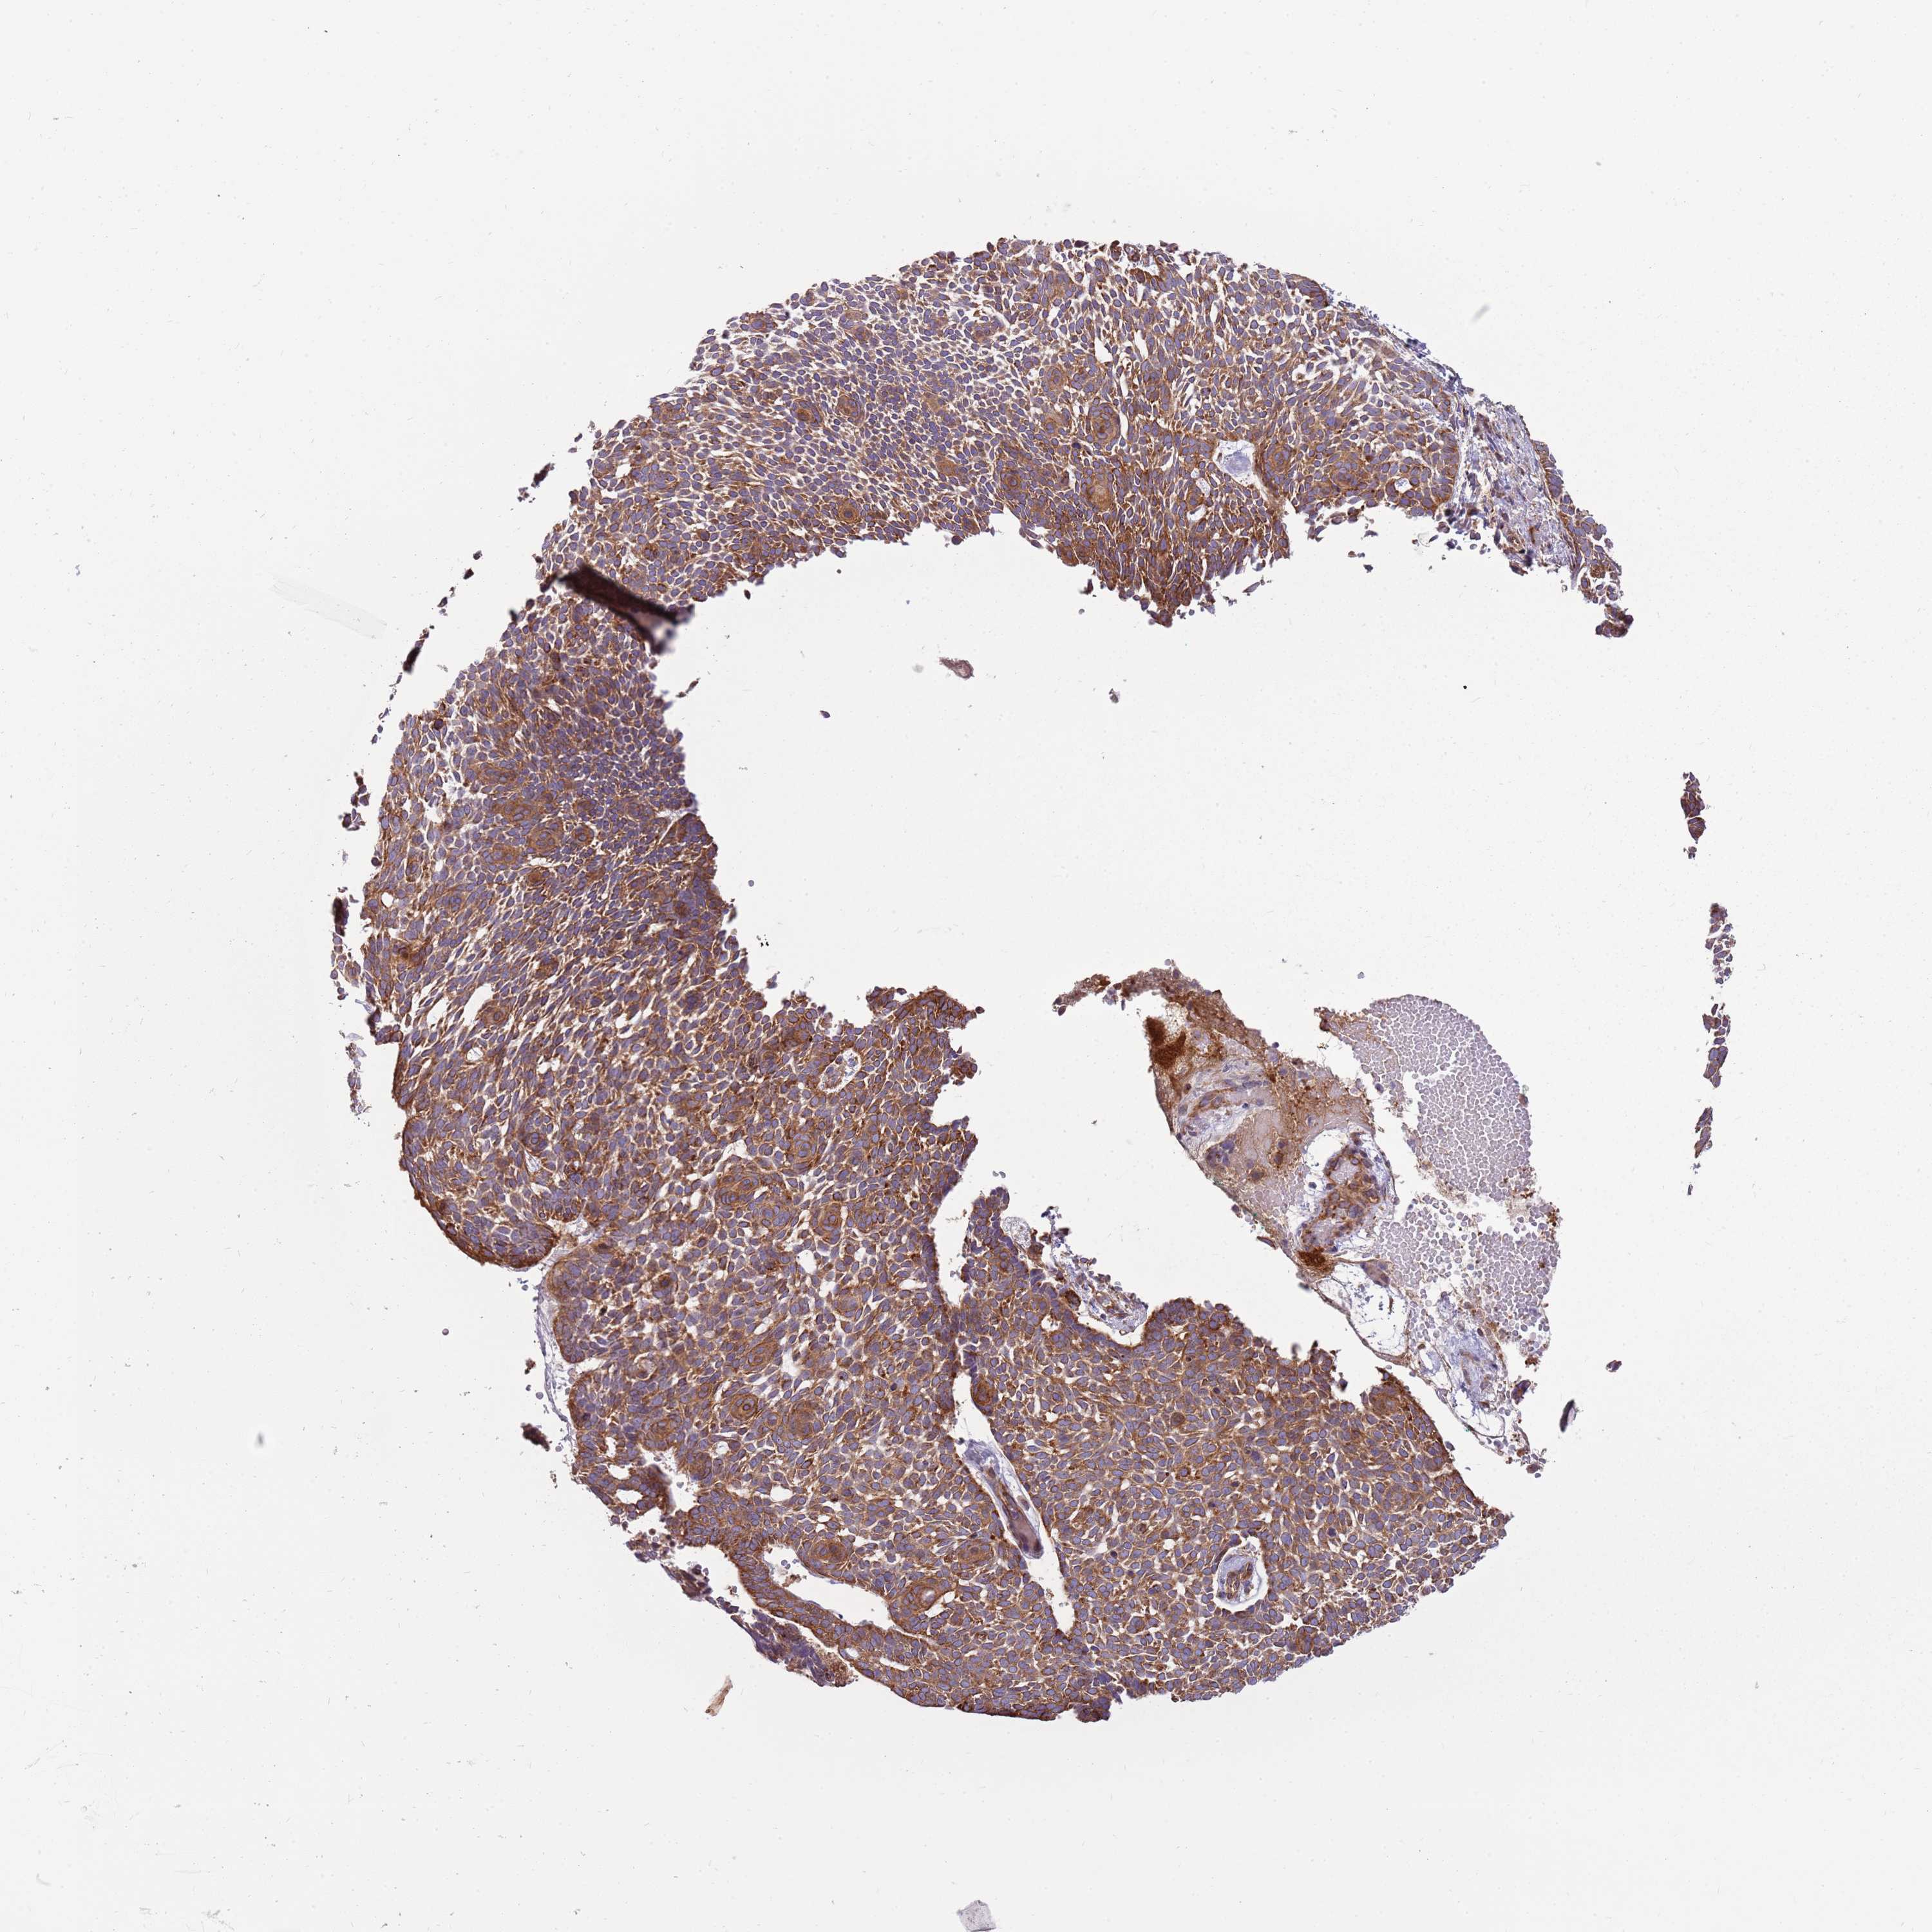

Basal cell and squamous cell cancer

SKIN CANCER - Protein expressioni

A mouse-over function shows sample information and annotation data. Click on an image to view it in a full screen mode. Samples can be filtered based on level of antibody staining by selecting one or several of the following categories: high, medium, low and not detected. The assay and annotation is described here.

Each image is clickable and will lead to virtual microscopy that enables deeper exploration of all samples and also displays staining intensity scores, fraction scores and subcellular localization as well as patient and tissue information for each sample.

Antibody HPA048904

Staining

Medium

Intensity

Moderate

Quantity

75%-25%

Location

Nuclear

Squamous cell carcinoma, metastatic, NOS